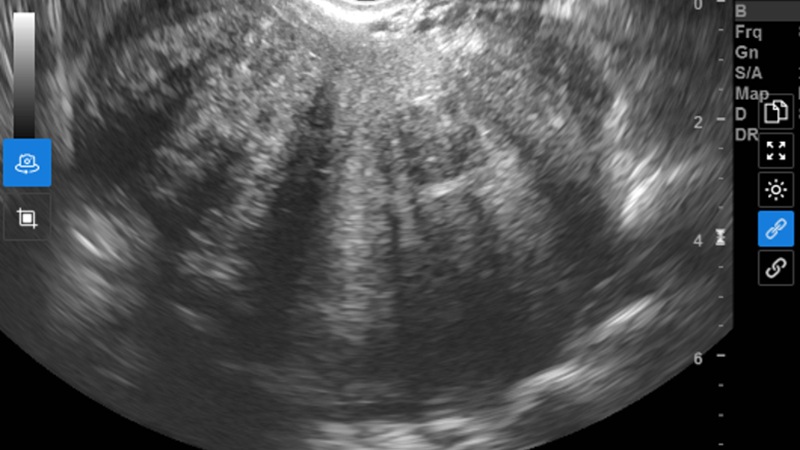

Kết quả siêu âm ghi nhận hình ảnh bất thường ở tử cung

Siêu âm ghi nhận hình ảnh đa u xơ tử cung, đồng thời phát hiện vùng tổn thương nghi lạc nội mạc tử cung ở buồng trứng trái kích thước 25 mm.